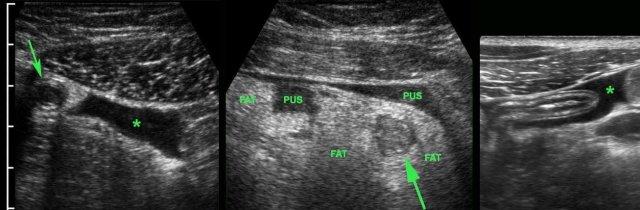

Một lượng nhỏ dịch trong phúc mạc giảm âm (*) có ít giá trị chẩn đoán và có thể gặp trong cả viêm ruột thừa cấp chưa thủng (trái) lẫn viêm ruột thừa thủng (mũi tên) (giữa), nhưng cũng có thể gặp ở bệnh nhân có ruột thừa bình thường (phải).

Lượng dịch lớn hơn, đặc biệt nếu khu trú và/hoặc đục, thường kèm theo liệt ruột khu trú hoặc toàn thể, là dấu hiệu nghi ngờ thủng.

Ở người phụ nữ 56 tuổi này với CRP 180, siêu âm phát hiện dịch trong phúc mạc đục (*) và có thể thấy ruột thừa viêm với sỏi phân (mũi tên).

CT xác nhận hai sỏi phân ở hố chậu phải với hình ảnh khí bất thường, nghi ngờ viêm ruột thừa thủng.